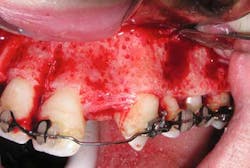

One way to help increase tooth movement in such a scenario is to use periodontally accelerated osteogenic orthodontics, a technique that involves creating corticotomies in the area of concern, which leads to a regional acceleratory phenomenon, or RAP. This results in increased bone turnover and decreased mineral content of the associated bone. This is often enough to help the patient get over the hump and finish the needed tooth movement.

The following case study shows a Caucasian male, age 15 at the beginning of treatment. He had a peg lateral incisor No. 7 and was congenitally missing tooth No. 10. The treatment plan consisted of positioning tooth No. 7 for a veneer and opening space for an implant to replace tooth No. 10. After 30 months of orthodontic treatment had elapsed, there was still insufficient room for implant placement. There was sufficient room for the crown of No. 10, but the roots of teeth Nos. 9 and 11 were still too convergent to allow implant placement. The patient was leaving for college soon and was anxious to have treatment completed. The decision was made to have a periodontist do a corticotomy surgery to accelerate the tooth movement.

Corticotomy surgery was done and distal root movement was initiated on tooth No. 11 using a lever arm and elastic power chain. Root divergence was accomplished in eight weeks, and implant placement was accomplished at that time. The occlusion was detailed and orthodontic appliances were removed a short time later.